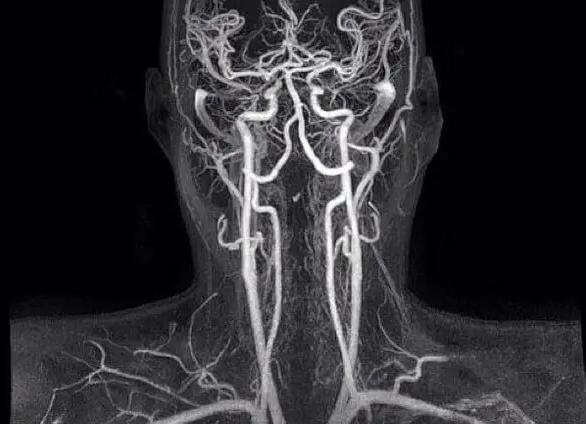

- УЗИ сосудов головы и шеи – методика дуплексного картирования;

- КТ и МРТ (компьютерная томография и магнитно-резонансная томография) с внутривенным контрастным усилением;

- церебральную ангиографию.

Последние два метода настолько информативны, что в 50–60% могут уловить признаки даже легкой степени ангиоспазма, если исследование проводится в момент приступа.